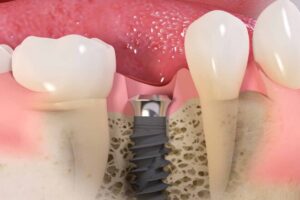

El tratamiento dental profesional es esencial para abordar las causas subyacentes de la halitosis. Estos procedimientos pueden incluir:

- Limpieza profesional (profilaxis): Eliminación de la placa y el sarro.

- Tratamiento periodontal: Raspado y alisado radicular para eliminar la infección en las encías.

- Obturaciones (empastes): Reparación de caries dentales.

- Extracciones: Eliminación de dientes irreparables que contribuyen a la halitosis.